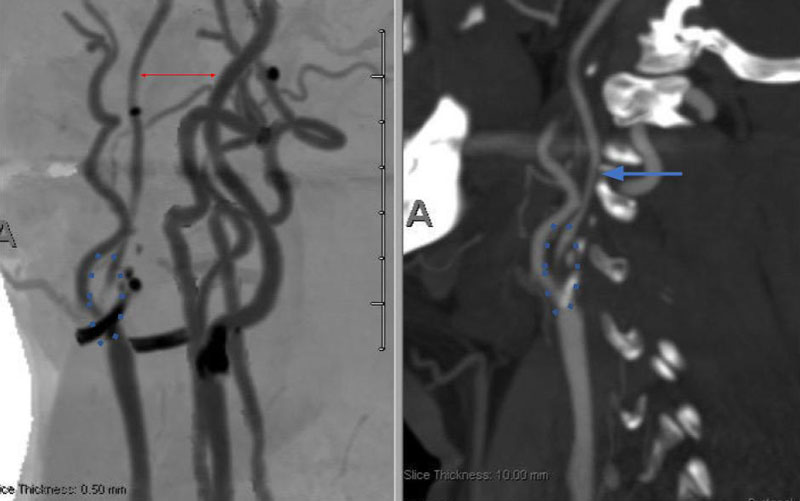

On admission, her initial CT scan was negative for stroke or hemorrhage, however a CTA demonstrated severe high grade 99% stenosis of the right Carotid bulb (ICA) with markedly diminished caliber of the cervical intracranial carotid artery secondary to calcified atherosclerosis without evidence of dissection (Figure 1).

Figure 1. A and B) CTA demonstrating severe ICA 99% stenosis (dotted) with flow-reduced diminution relative to the left ICA (red arrows) and distal plaque extension to C2 level.